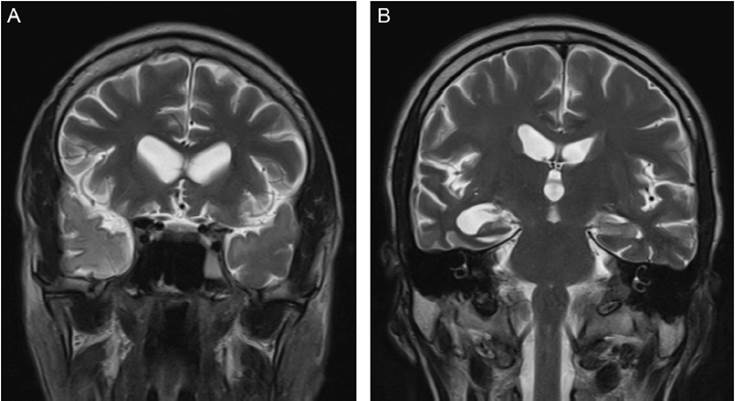

Imagenología

A pesar de que hasta 2 tercios de los pacientes con neurosífilis tienen reportes normales en la tomografía computarizada, la resonancia magnética ola angiografía20, la neurosífilis puede tener una amplia variedad de presentaciones en los diferentes tipos de ayudas imagenológicas cerebrales21,23.

Los cambios imagenológicos que tienen que ver con la neurosífilis son particularmente variables, pero por su mayor frecuencia destacan la atrofia encefálica leve-moderada, los infartos cerebrales típicamente lacunares o en el territorio de la arteria cerebral media, las lesiones inespecíficas en la sustancia blanca y la prominencia periventricular de esta, la hidrocefalia, las gomas cerebrales, la esclerosis mesial-temporal, el realce leptomeníngeo, los granulomas leptomeníngeos, la periostitis orbitaria gomatosa y la periostitis que afecta a la cápsula óptica20,23.

No obstante, algunos autores han planteado la posibilidad de que muchos de los hallazgos anteriormente mencionados pueden deberse a posibles coinfecciones, como se puede observar en pacientes con infección por el VIH, y siempre se debe tener en cuenta que existe una amplia gama de diagnósticos diferenciales una vez se encuentran lesiones de cualquier tipo en las imágenes cerebrales de ciertos grupos de pacientes22.

Asimismo, en pacientes sin infección por el VIH pueden darse diagnósticos como encefalitis por el virus del herpes simple, esclerosis mesial temporal, leucoaraiosis, hidrocefalia de presión normal y glioblastoma multiforme21.

En las figuras 2-3 se presentan imágenes correspondientes a casos tratados en el Hospital Psiquiátrico Universitario del Valle en los cuales se llegó al diagnóstico de neurosífilis.